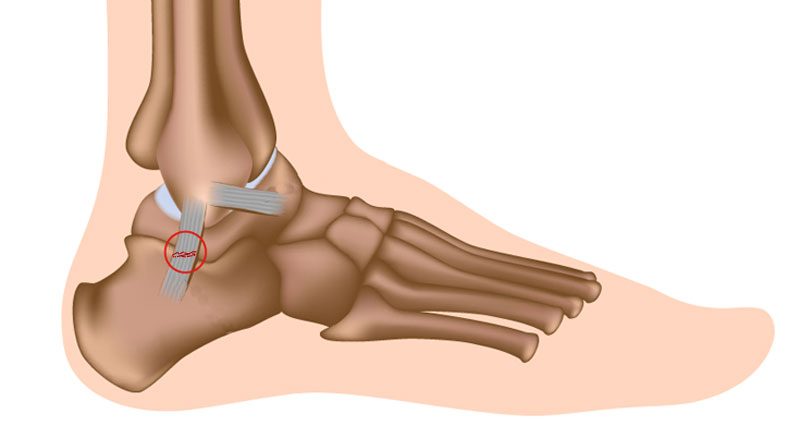

Sprained heel sale, Lateral Ankle Sprain Complete Physio sale

Lateral Ankle Sprain Complete Physio

Ankle Sprain